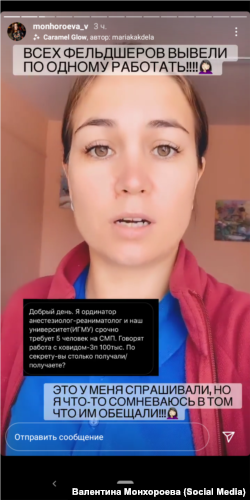

– Люди задыхаются, у них сатурация 80–85%, а бригады скорой помощи вынуждены бросать их, оставлять их дома. Потому что везти некуда! Ни в одной из больниц Иркутска нет мест. Хотя по всем показаниям это тяжелые больные – им госпитализация нужна, под кислород, – сотрудница БСМП Иркутска Валентина Монхороева (раньше работала в бригаде скорой помощи, сейчас – в диспетчерской) записала видеообращение к губернатору области с требованием решить проблему с коечным фондом. – Накануне 200 машин в очереди стояли, 200(!). Была бы я в бригаде – поехали бы прямо к зданию администрации. Куда-то же надо больных везти.

Фельдшеру из Иркутска Валентине Монхороевой после ее прямого эфира в соцсетях с запросом к властям области что-то сделать с дефицитом коечного фонда позвонили из Минздрава региона.

– Сказали: "Не накаляйте обстановку!". То есть меня услышали, они все знают, но делать с проблемой ничего не будут, – возмущена медработник.